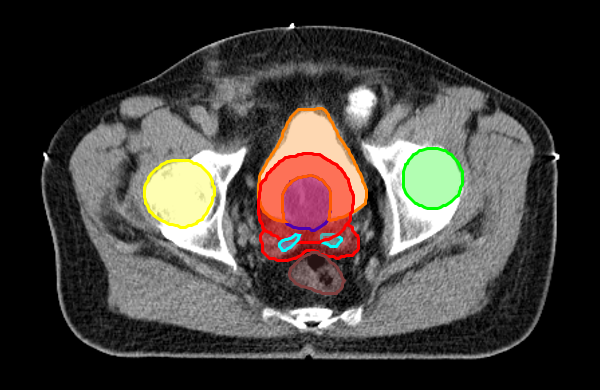

Radiotherapy planning software is responsible for generating contours for protection of risk organs and contours for tumor areas. To exemplify this process, below are the contours and radiations for you to interact with! Change the position of the slide (green circle) and check the outlines and rays (radiation) generated with SIPRAD for a radiotherapy treatment.

Generation of protective contours of risk organs and tumor areas.